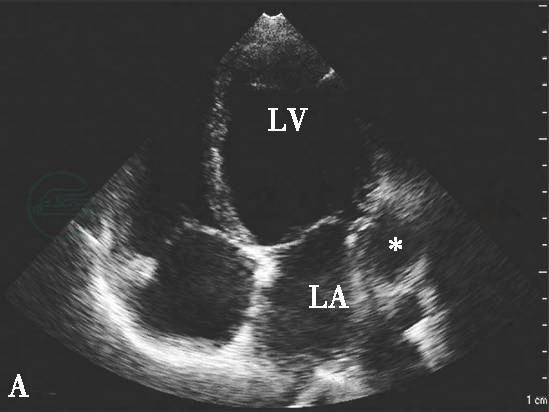

图2心肌梗死后左心室游离壁破裂合并假性室壁瘤形成二维切面图像

心尖四腔心切面显示左心室侧壁破裂形成巨大假性室壁瘤(星号示),其内可见附壁血栓(三角示)。LA.左心房;LV.左心室。